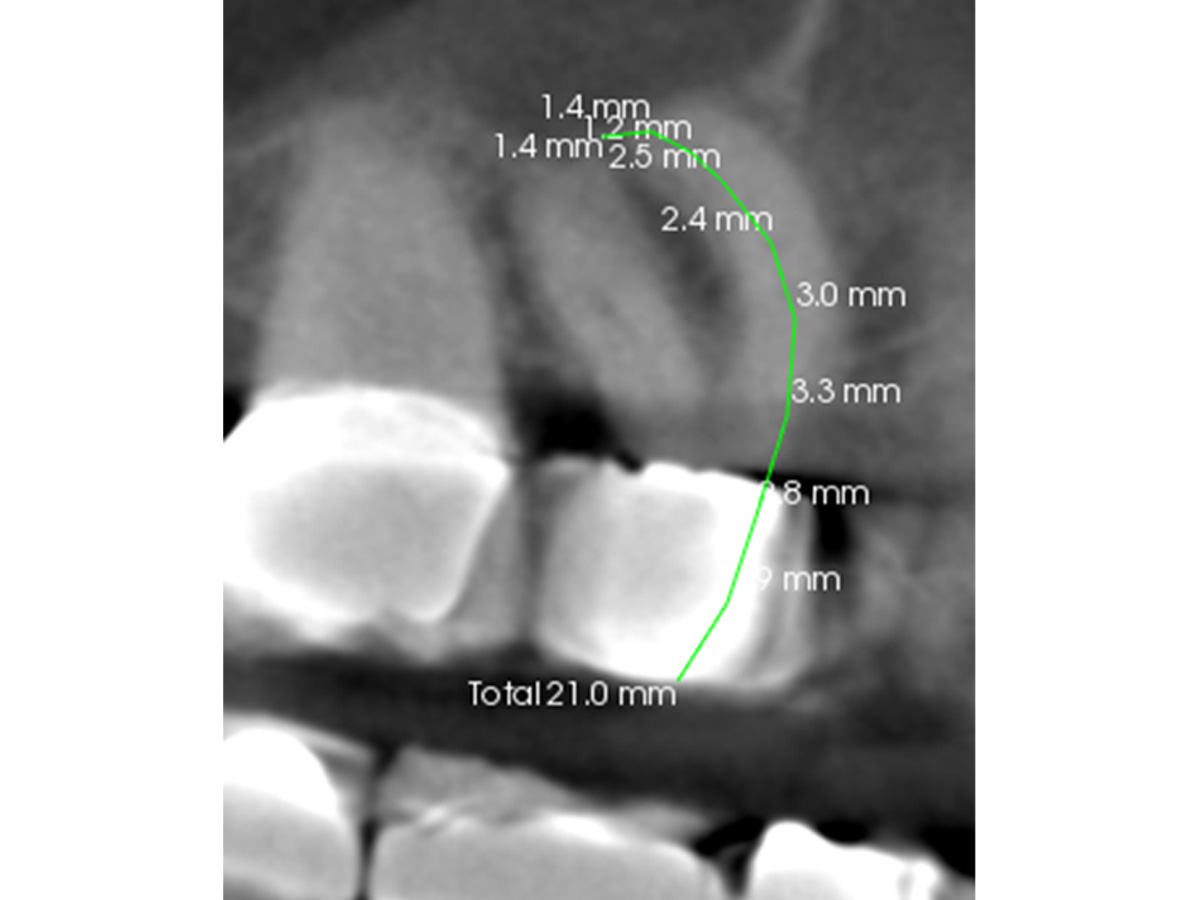

Abbildung 1

Röntgenologisch (Einzelbild 16-17) sind zwei Einzelkronen erkennbar. Keine zusätzliche diagnostische Information.

Abbildung 2

Nach der DVT-Untersuchung (Kodak 9000 3D, Auflösung 0,076 mm) bestätigte sich eine apikale Parodontitis an Zahn 16 palatinal. Eine Wurzelkanalbehandlung an Zahn 16 ist indiziert.

Abbildung 3a

Obliterierte bukkale Kanäle...

Abbildung 3b

...und eine starke Krümmung mesiobukkal.